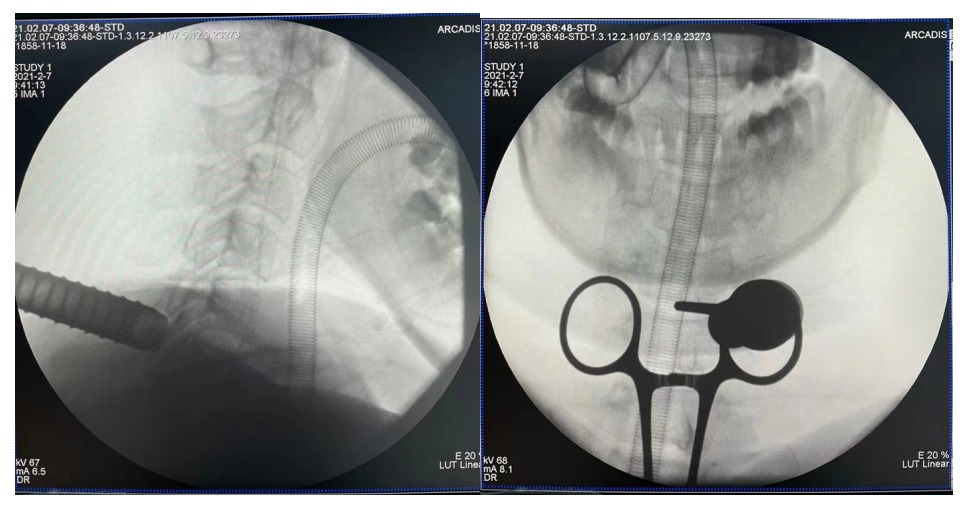

术前